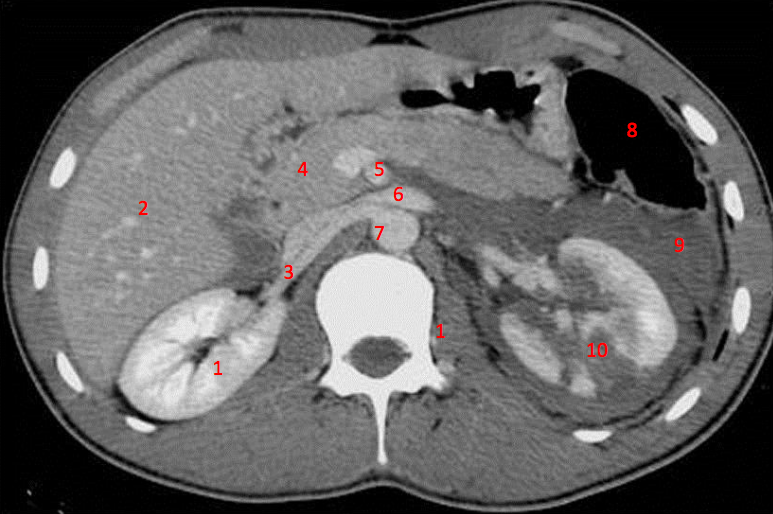

Number 1?

R Kidney

Number 4?

Rt diaghragmatic crus

Number 5?

Rt ureter

Number 9?

Superior mesenteric artery

Rectus abdominus

Number 8?

Descending colon